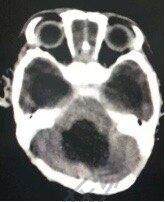

早產(chǎn)兒腦室內(nèi)出血是一種嚴(yán)重威脅患兒生命和存活后生活質(zhì)量的疾病,發(fā)生率因報(bào)道病例數(shù)量不同范圍在5-90%之間,死亡率高。存活下來(lái)的患兒可能出現(xiàn)癲癇、智力低下和運(yùn)動(dòng)障礙等,文獻(xiàn)報(bào)道 25-80% 可出現(xiàn)腦積水,合并室旁腦白質(zhì)病變的病人有75%遠(yuǎn)期將出現(xiàn)神經(jīng)功能障礙。根據(jù)Papile分級(jí)將腦室內(nèi)出血分成四級(jí),I級(jí):單或雙側(cè)室管膜下胚胎生發(fā)層組織出血(SHE);Ⅱ級(jí):SHE破入腦室,引起IVH;Ⅲ級(jí):IVH伴腦室擴(kuò)張;Ⅳ級(jí):Ⅲ級(jí)IVH伴腦實(shí)質(zhì)出血(即腦室周圍髓靜脈出血性梗死)。在糾正凝血功能障礙后,目前治療腦室內(nèi)出血的方法有:反復(fù)腦室穿刺或腰穿放液、皮下安裝儲(chǔ)液囊反復(fù)抽吸、腦室內(nèi)注射尿激酶溶解血塊等,以上治療適合病情較輕的患兒,最主要的缺點(diǎn)是使顱壓波動(dòng)過(guò)大,腰穿還可能誘發(fā)枕大孔疝。也有文獻(xiàn)認(rèn)為這些治療并不能減少致殘率和死亡率以及腦積水發(fā)生率。小兒神經(jīng)外科治療腦室出血最確切可靠的治療是側(cè)腦室持續(xù)外引流,如果腦室鑄型還應(yīng)開顱清除血腫再持續(xù)外引流,并根據(jù)腦積水發(fā)展情況適時(shí)行分流術(shù),盡早治療對(duì)預(yù)后影響很大。雖然存在分流管堵塞、感染以及分流管依賴等合并癥,腦積水分流術(shù)仍然是腦室出血后合并腦積水的唯一有效的治療。存活后的患兒根據(jù)病情除定期復(fù)查外,還需藥物治療和康復(fù)治療。國(guó)外一組214例重度腦室出血患兒中,94例為三級(jí),存活率78%,存活患兒中腦癱5例,矯正后24個(gè)月DQ為99。120例為四級(jí),存活率為53%,其中腦癱37例,DQ是95。圖示為1例早產(chǎn)患兒,生后發(fā)生自發(fā)性腦室內(nèi)出血,隨后出現(xiàn)重度腦積水于生后1個(gè)月急診收入我科,入院后我們立即行外引流術(shù),腦脊液正常后行側(cè)腦室腹腔分流術(shù),術(shù)后2個(gè)月復(fù)查腦室恢復(fù)至正常大小,患兒發(fā)育良好。